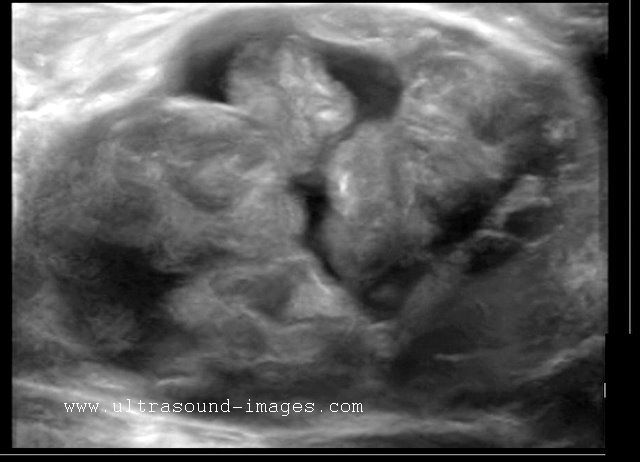

Carcinoma of breast

Malignant lesion of the breast.

These ultrasound images reveal a hypoechoic, poorly defined, irregular mass in the breast. There is also evidence of acoustic shadowing posteriorly. These findings on sonography suggest malignant mass of the breast. Images courtesy of Dr. Nirmali Dutta, UAE.